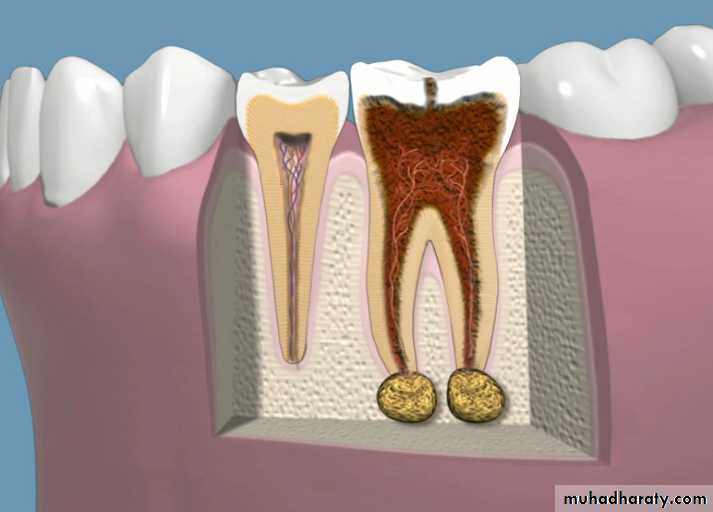

A mass of chronically inflamed granulation tissue at the apex of a nonvital tooth.

Most lesions are discovered on routine radiographic examination.A well-defined radiolucency of bone apical to the offending tooth. Loss of the apical lamina dura.

The lesion may be circumscribed or ill defined.

Inflamed granulation tissue surrounded by a fibrous connective tissue wall.Dense lymphocytic infiltrate that is intermixed with neutrophils, plasma cells and giant cells.

Epithelial rests of Malassez may be identified within the granulation tissue.